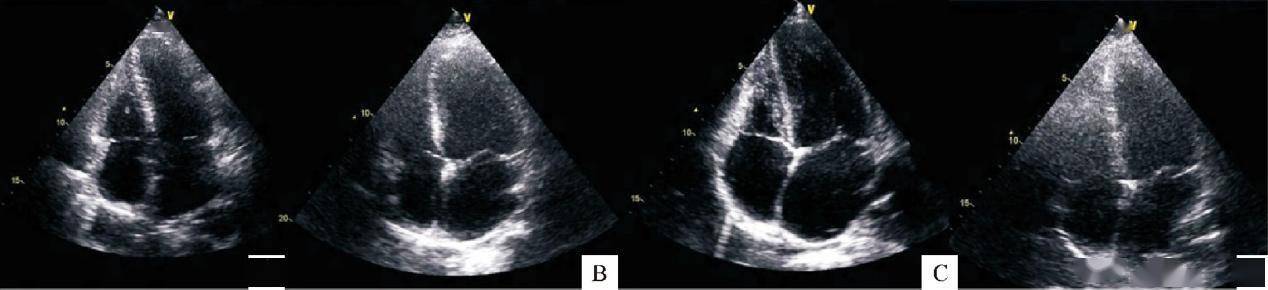

不同类型妊娠期高血压疾病的母体心脏形态学变化(A:轻度先兆子痫组;B:重度先兆子痫态组;C:慢性高血压组;D:妊娠期高血压组)[4]